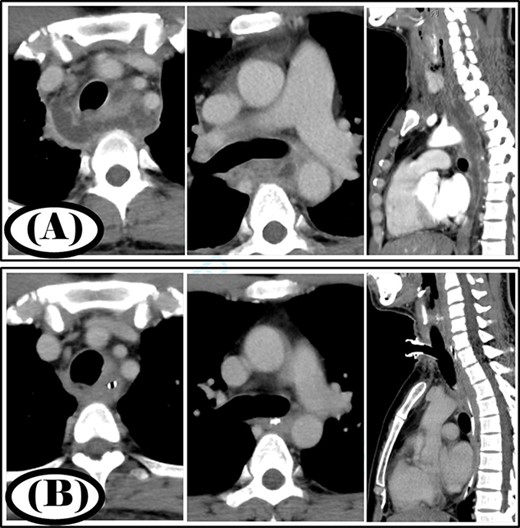

A 35-year-old man was diagnosed with a cervical abscess and initially underwent cervical drainage. The next day, he developed upper gastrointestinal perforation that was covered with an omental patch in a laparoscopic procedure. The cervical abscess did not improve and chest CT revealed that the infection had developed into the mediastinum (Fig. 2A). The patient was diagnosed with type II DNM and underwent mediastinal drainage using a cervical approach 3 days later. Initial antibiotic therapy consisted of meropenem at 9 g/day for 6 days as broad-spectrum antibiotic therapy. After Streptococcus anginosus group was detected in the mediastinal abscess cavity, the antibiotic was changed to ampicillin/sulbactam 12 g/day and was administered via intravenous infusion for 15 days. Continuous irrigation with saline (2 L/day) was initiated immediately post-surgery; however, 500 ml per day of saline was used for irrigation on the first 4 days. The duration of irrigation, drainage and hospital stay were 4, 16 and 39 days, respectively. Five weeks post-surgery, cervicothoracic CT showed no abscess cavity and an improvement in infection (Fig. 2B).

Case 2: pre- and post-treatment cervicothoracic CT; (A) pre-operative cervicothoracic CT and (B) cervicothoracic CT 5 weeks after treatment.